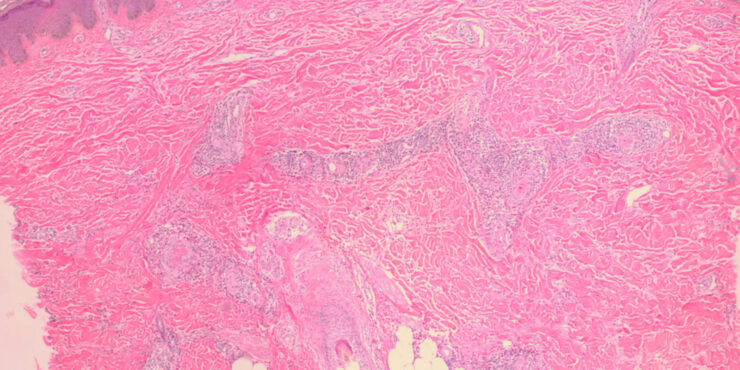

Cutaneous B cell lymphoma = اللمفوما الجلدية بائية الخلايا